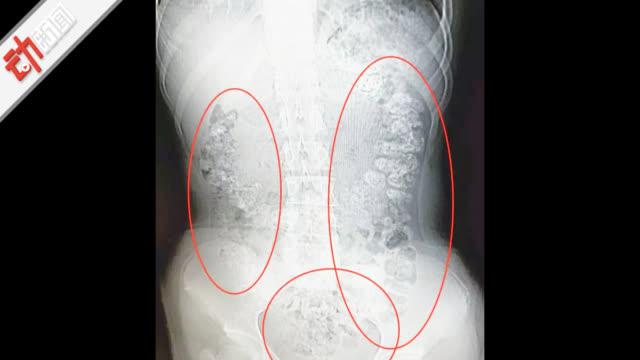

14岁女孩喝奶茶肚子疼5天 胃内现百余颗"珍珠"

图片尺寸640x360